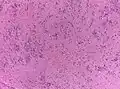

- Основным гистологическим типом является истинная эпендимома , для которой типично наличие периваскулярных и истинных «розеток». Периваскулярные «розетки» («псевдорозетки», «лучистая корона») состоят из клеток новообразования, которые располагаются вокруг кровеносных сосудов. В истинных «розетках» опухолевые клетки находятся вокруг каналов, которые выстланы эпендимарными клетками.